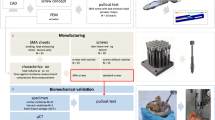

A newly developed BISS screw (bipolar induction screw system) with integrated coil and electrodes was compared to a standard cannulated screw used in the traditional technique. The strength of BISS screws (n=6) and of cannulated screws (n=6) was evaluated in comparative biomechanical tests. Examinations consisted of torsional and static and dynamic cantilever tests. All screws were made of the same material (TiAl6V4) and had identical outer dimensions.

The aim of the study was to prove the mechanical stability of the BISS system. In order to determine the mechanical strength of bipolar induction screws and of electrical isolation of the adhesive film between the tip and shaft of the screw, static and dynamic bending tests were carried out. We also determined the static torsion shearing strength of the adhesion film.

The basic body of a BISS screw is a cannulated spongiosa screw (titanium basic alloy, TiAl6V4), with a transducer coil being inserted into its hollow space. The cannulated screw (including screw head, shaft and thread face) is used as the first electrode. Subsequent to implanting the coil, the tip of the screw (without thread) is adapted as the second electrode, using an adhesive which is electrically isolating (epoxy resin, named Hysol, Dexter Co., USA) into the other part of the screw (Fig. 2). The BISS screw (GEOT, Germany) is available in different lengths and diameters. A size suitable for the treatment of necrosis of the femoral head was tested in the examinations relevant for this study. In a control group, cannulated spongiosa screws—the body of the BISS screws—with a length of 80 mm, an external diameter of 6.5 mm, a (tapping) spongiosa thread length of 44 mm, and a core diameter of 5 mm (manufactured by DePuy, UK) were used.

The static bending tests were carried out on six BISS screws and six cannulated spongiosa screws (hollow core screws; HS) using a universal testing machine (Wolpert TZZ 707, load cell 50 kN) (Fig. 3). The screws were set in a drill chuck, with the screw’s longitudinal axis orthogonally adjusted to the inspection stamp (radius 3 mm) and strain direction. The load of the bipolar induction screws was fixed to the end of the screw, with a free clamping length of 25.5 mm. In order to avoid a localised, uni-sided, plastic deformation of the thin-walled end of the spongiosa screws, a journal of 13 mm length was fitted into the end of the screw to allow for a more even introduction of force. The strain was exerted at the same free clamping length of 25.5 mm at a test velocity of 5 mm/min until the extension maximum was reached. During the test a force-deformation diagram was recorded.

For the dynamic free bending tests we also used six cannulated (HS) and six BISS screws. The dynamic bending tests were carried out in a servo-hydraulic test machine (Roell Amsler 2151, load cell 20 kN) at room temperature in air. The test set-up was identical to that for the static bending tests. However, the load on the bipolar induction screws was applied to the end of the screw in a pulsating manner, with a test frequency of 5 Hz. The test was continued until the level of endurance determined prior to the test was reached or the screw burst. During the test, maximum and minimum loads as well as maximum and minimum lowering of the inspection stamp were recorded. The maximum loads applied were around 400 N, which equals a maximum bending moment of 10.2 Nm. This corresponds to about 50% of the average bending moment obtained during static tests as far as the extension maximum was concerned (20.5 Nm for BISS screws, 18.7 Nm for cannulated screws).

The static torsion shearing strength was determined using a universal testing machine (Wolpert TZZ 707, load cell 50 kN) at room temperature. The samples (n=7) were fixed between two drill chucks, one of which was connected with the machine crosshead, the other with a torque detector (Burster 8628, max. torque 100 Nm) and a swing angle provider (Megatron MA 751) (Fig. 3). Apart from that, the specimens were exposed to an axial tension load of 10 N using an universal testing machine. The load on the samples was introduced at an angular velocity of 0.1°/s until the adhesive film came apart. Torsional moment and torsional angle were recorded for the whole test period by using a personal computer.

The new BISS system is based upon the technical foundations of the electroinduction method introduced by Kraus and Lechner [14] and Ascherl [1] (frequency 20 Hz, magnetic induction 5 mT, actual voltage 700 mV, internal resistance <100 Ω). Also in this context, extracorporeally applied electromagnetic alternating fields create a flow of current intracorporeally in the target tissue by way of the transformer principle. The successful utilisation of this principle in the context of bony tissue requires a reproducible application of the electrodes. By using the newer system, it is possible to reduce the parts to be implanted (Fig. 7), which results in a simpler application method and last but not least in a much easier way of removing the implants.